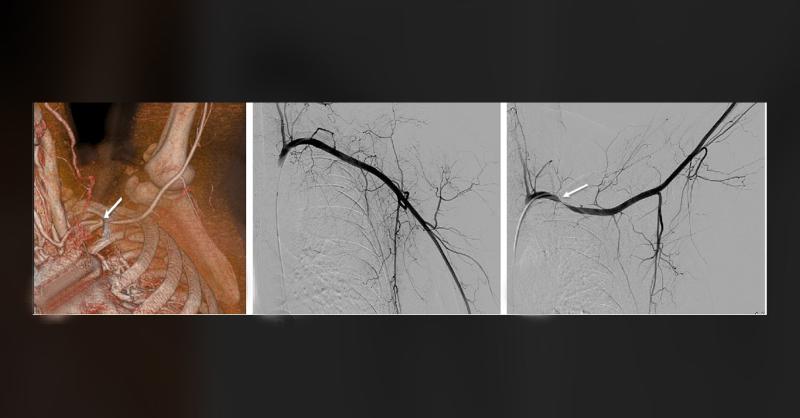

A 48-year-old woman complained of tingling in her left arm when she raised it. A month earlier, she had fallen from a 2-meter-high ladder and broken her fourth and fifth ribs on the left side. After the fall, her chest pain got worse and she felt tingling in her arm, especially when lifting it. Tests showed that a major blood vessel in her chest, t